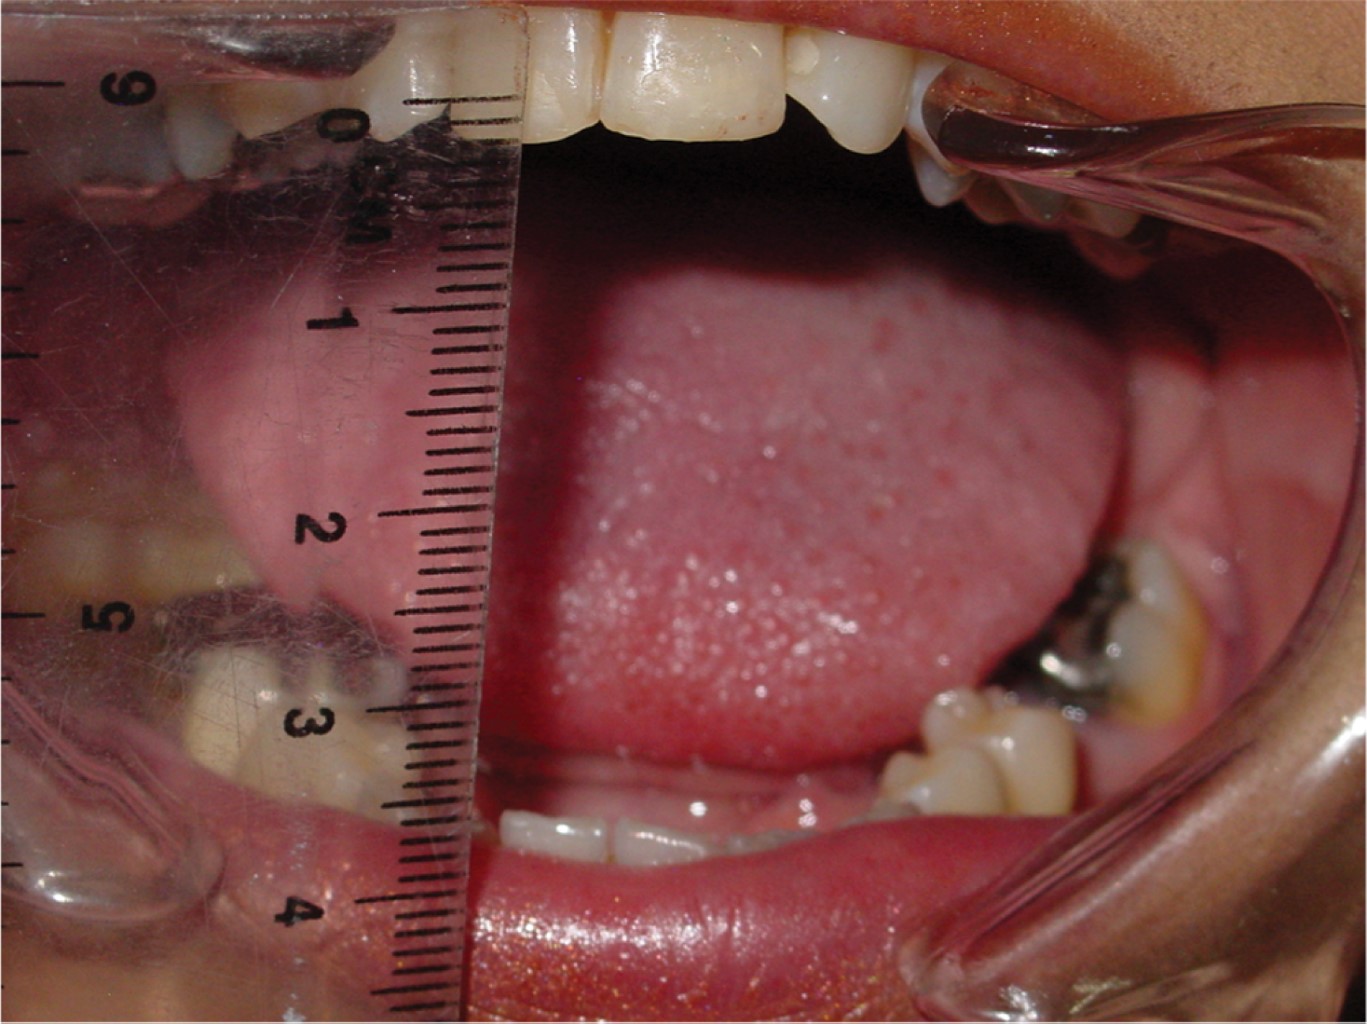

Introduction: the objective is to present a case of total alloplastic replacement of the temporomandibular joint with personalized prostheses (TMJ Concepts®) in rheumatoid arthritis and injection of botulinum toxin type A for protection of prostheses against bruxism. Clinical case: we present the case of a 44-year-old female patient with severe bilateral temporomandibular joint (TMJ) resorption due to advanced stages of rheumatoid arthritis, which was managed by total replacement with a personalized alloplastic prosthesis (TMJ Concepts®, Ventura CA) and infiltration of botulinum toxin type A (Botox, Allergan, Ireland). Results: painful symptomatology was eliminated immediately and pre-surgical oral opening changes from 2 to 50 mm were achieved in the first year after botulinum toxin placement; 12 years later, the prosthesis is stable and functional. Conclusions: botulinum toxin can be a simple, safe, and effective adjuvant treatment in patients reconstructed with personalized alloplastic prostheses.

Figure 2